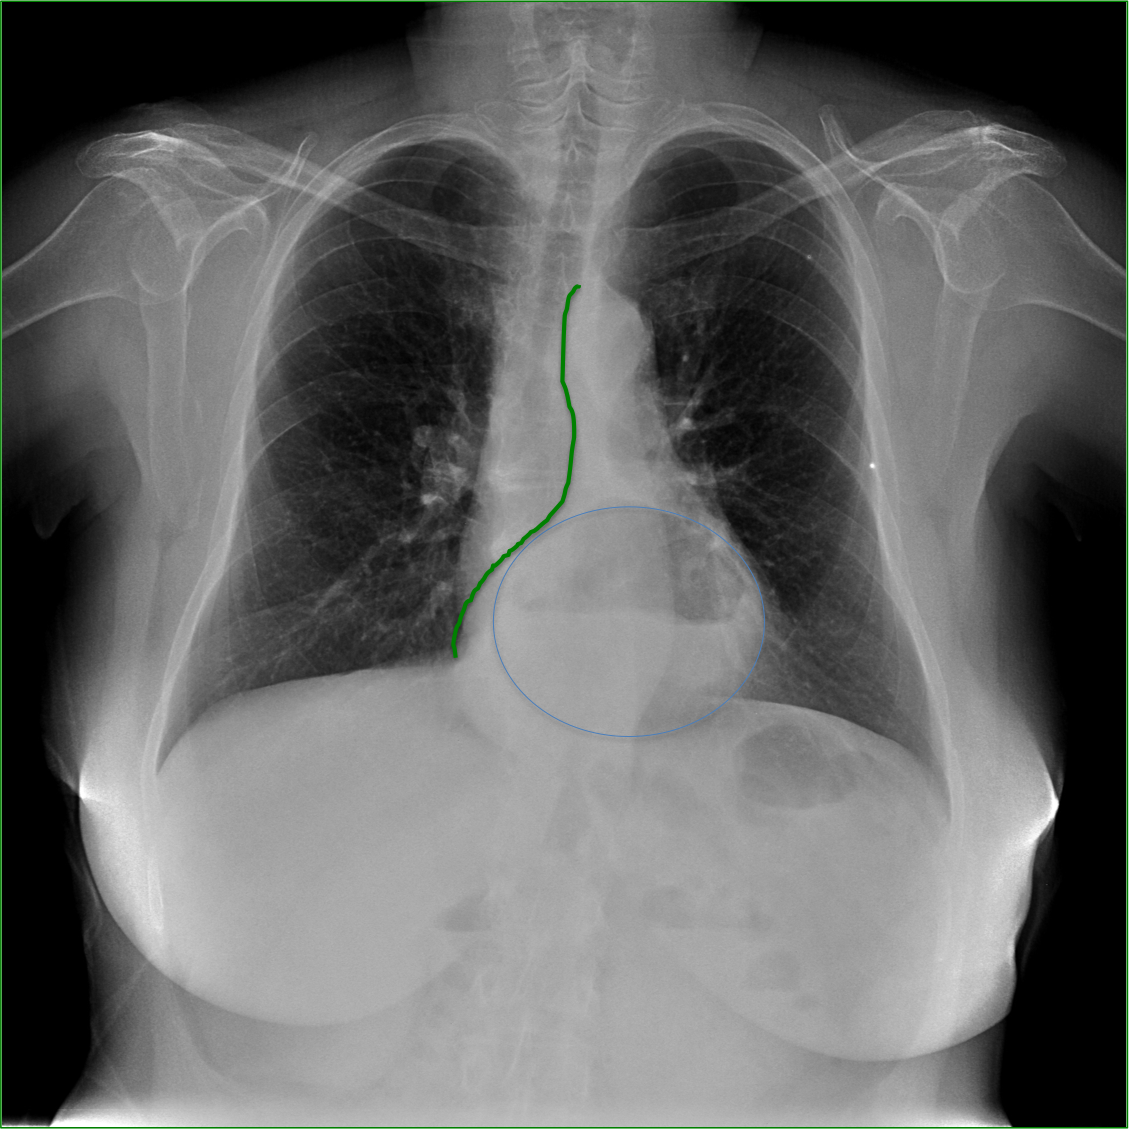

Mismo paciente, al cual esta vez se le ha tomado una radiografía en PA y en sedestación. Observar como las clavículas están equidistantes a las apófisis espinosas y como ha desaparecido el velamiento del pulmón izquierdo.

Por otra parte, paciente presenta una cardiomegalia y un discreto ensanchamiento del mediastino es probable relación con cambios postquirúrgicos.